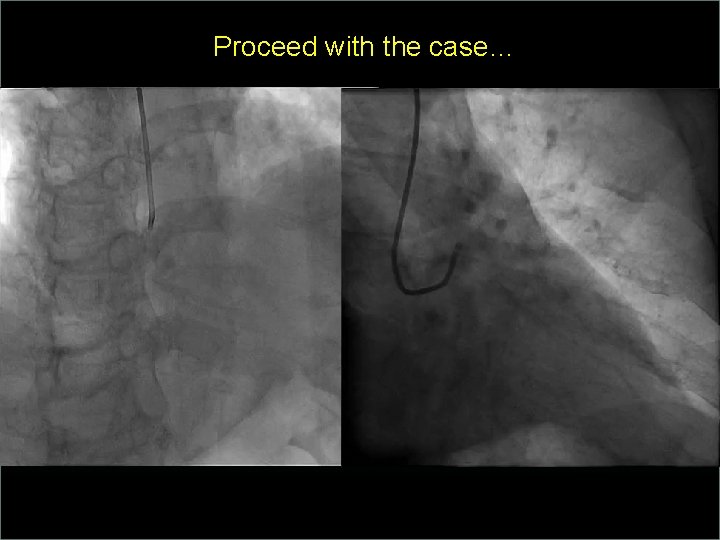

Transradial Interventions Difficult Anatomic Substrate Challenges and Solutions